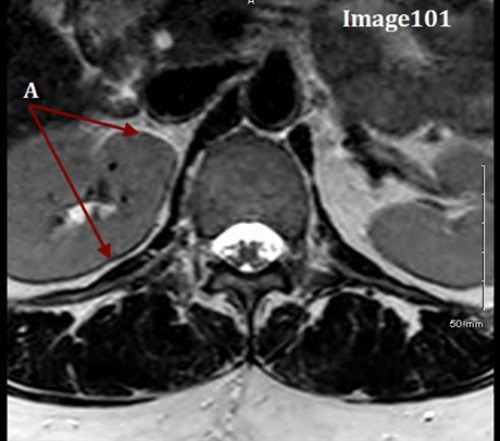

The artifact in Image 101 is caused by:

A. Local eddy currents due to the increased conductivity of body tissue

B. When a small matrix is used, it incompletely digitizes the echo by the end of the acquisition

C. Differing frequencies of fat and water

D. The imperfect shape of RF slice profiles, which leads to an unintended excitation of an adjacent slice or tissue

Letter A in Image 101 is pointing to the dark and bright bands along the border of the vertebral body. What type of MR artifact is this?

A. Partial volume averaging

B. Gibbs truncation

C. Cross talk

D. Wraparound (aliasing)

E. Chemical shift